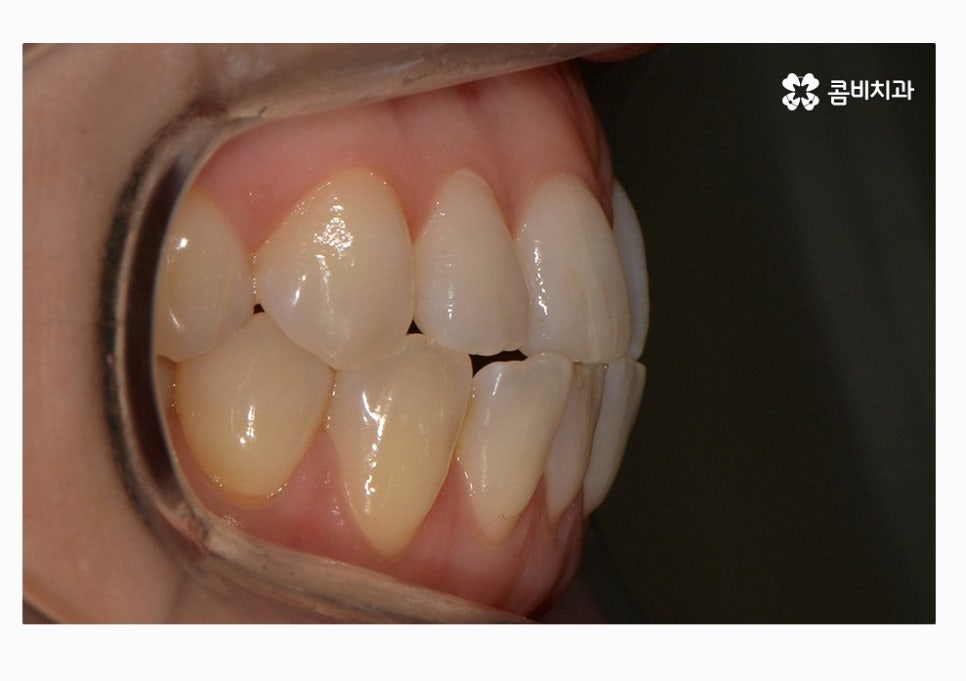

부정교합의 종류도 다양하지만 오늘 보시는 케이스의 경우

절단교합 + 3급부정교합에 해당하며 아랫니가 과하게 앞으로

돌출된 경우에는 치열뿐 아니라 주걱턱과 같이

얼굴형에도 영향을 줄 수 있어요.

치열 사진을 볼 때 정면보다는 옆모습으로 볼 때

아래 어금니가 위 어금니보다 앞으로 나와있고

앞니 교합이 제대로 맞물리지 않는다는 것이 눈에 띄게 나타나는데